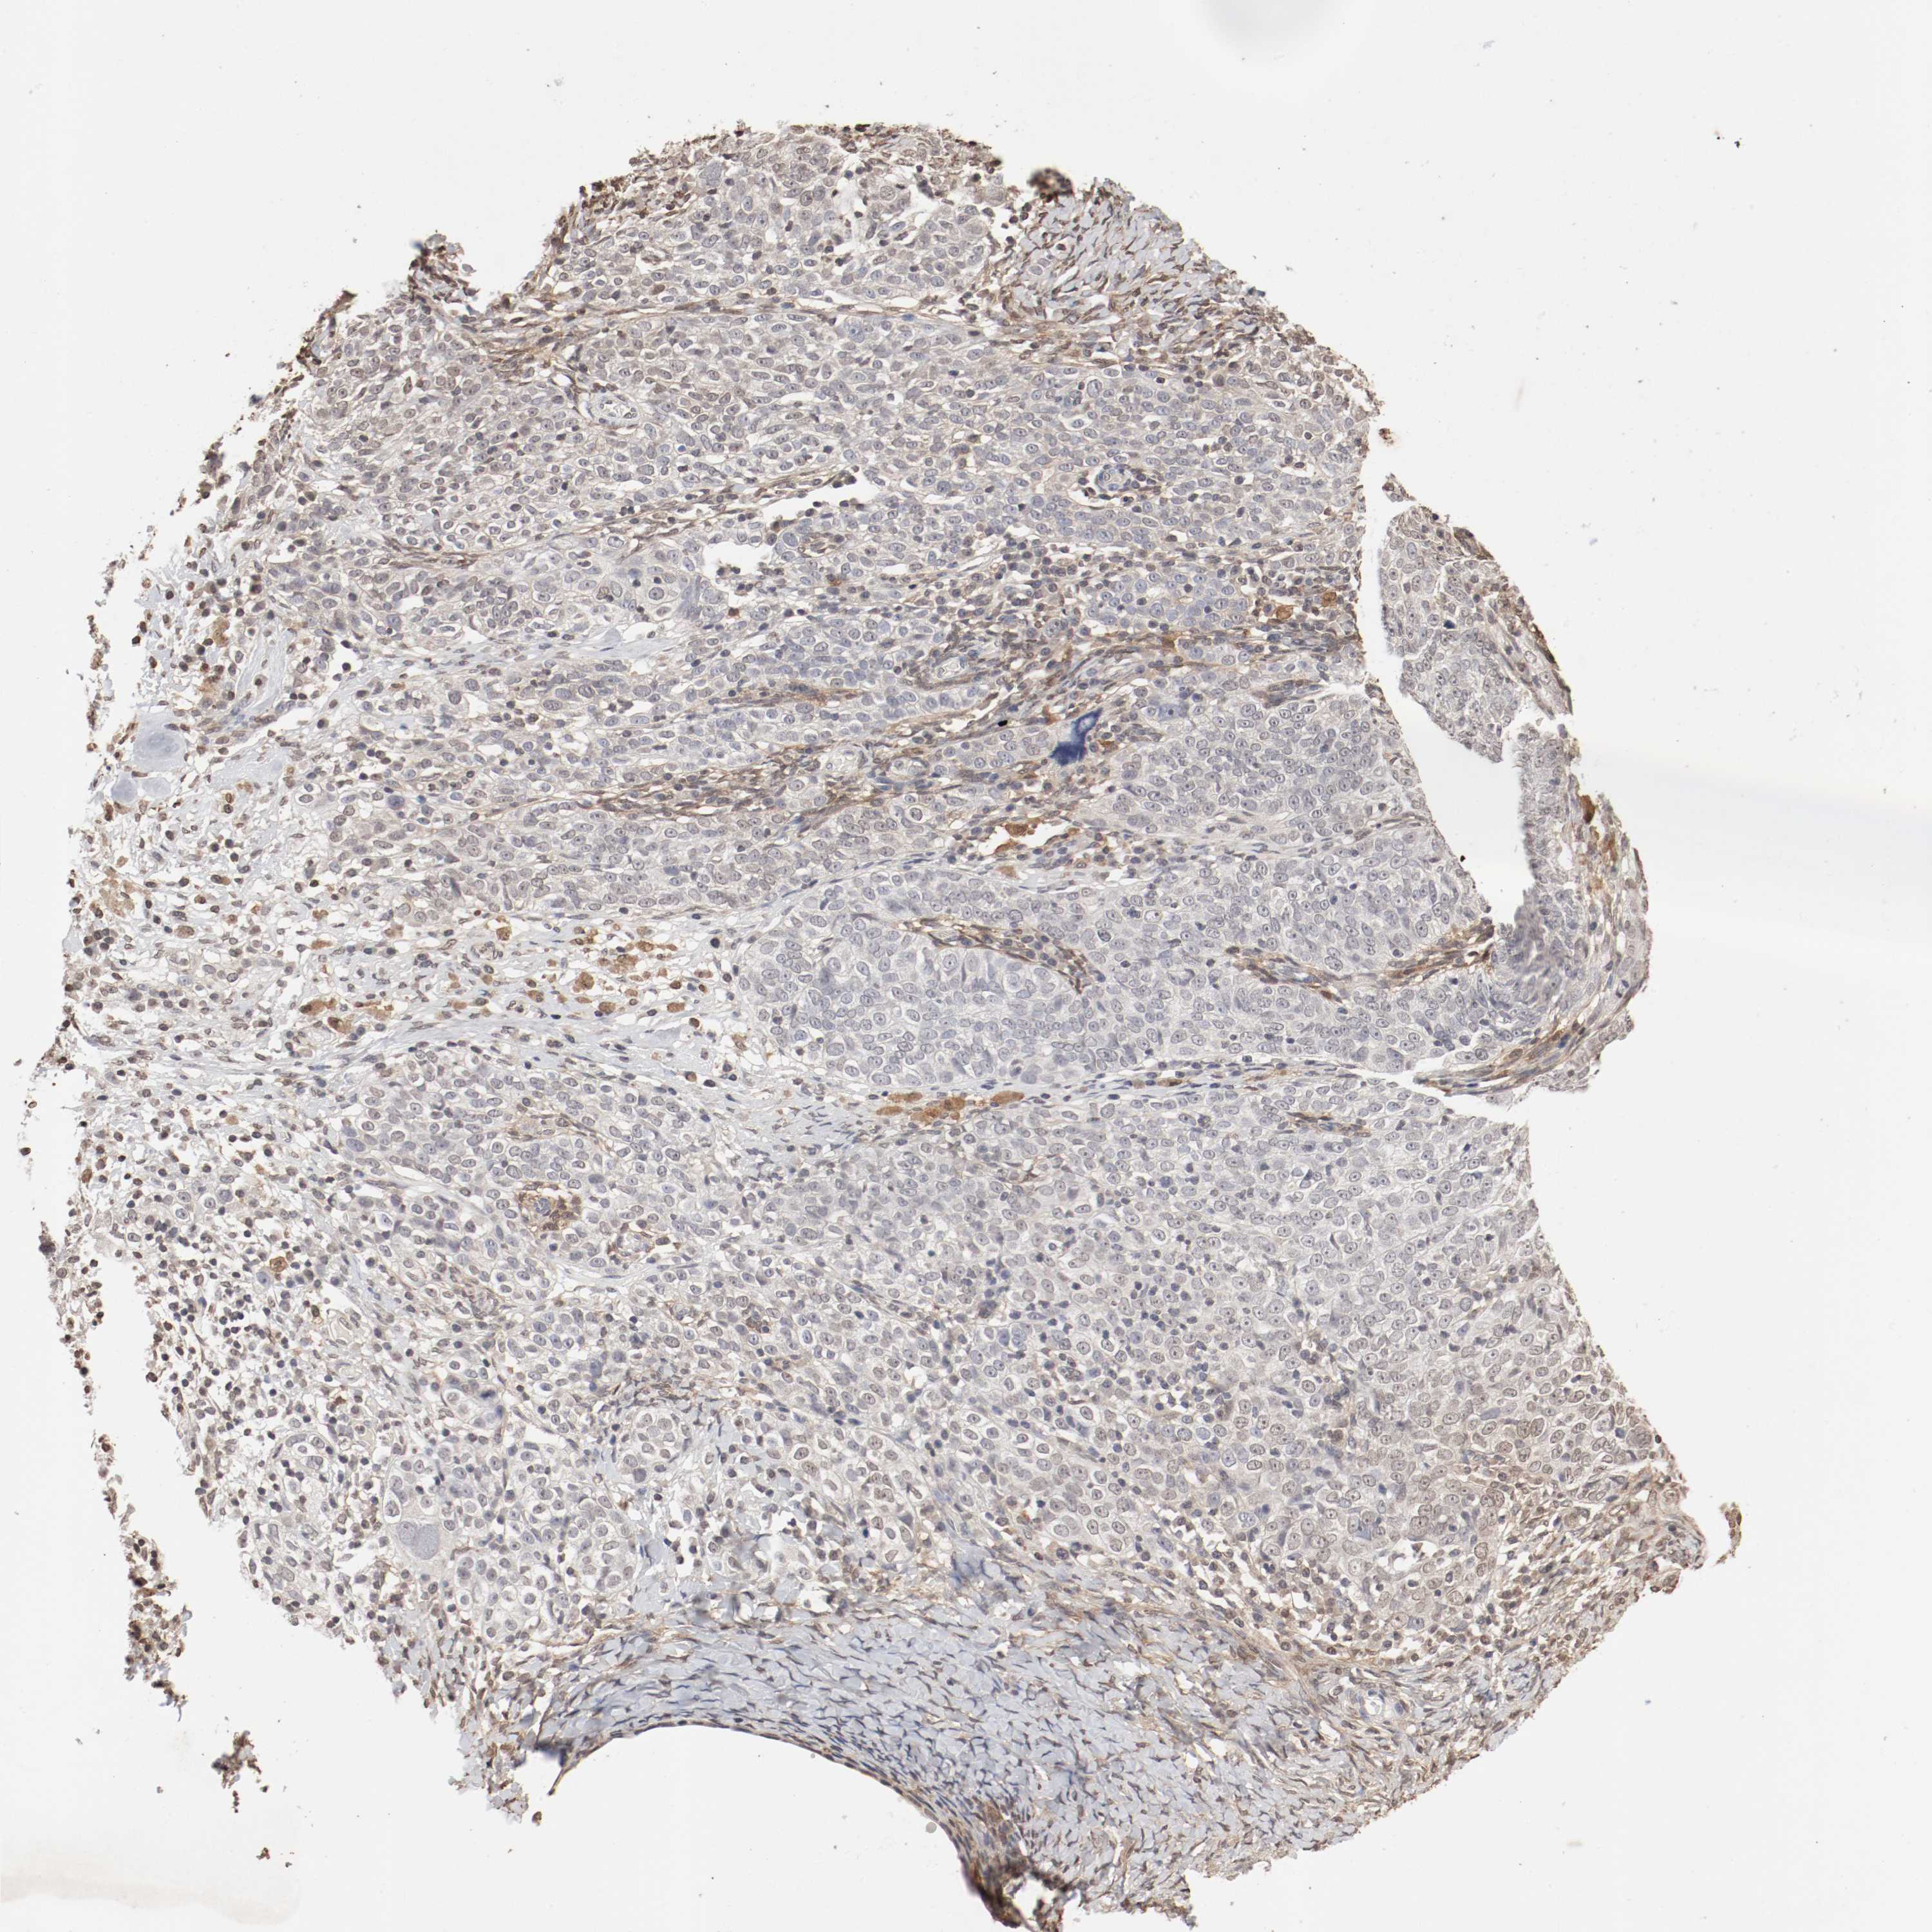

OVARIAN CANCER - Protein expressioni

A mouse-over function shows sample information and annotation data. Click on an image to view it in a full screen mode. Samples can be filtered based on level of antibody staining by selecting one or several of the following categories: high, medium, low and not detected. The assay and annotation is described here.

Note that samples used for immunohistochemistry by the Human Protein Atlas do not correspond to samples in the TCGA dataset.

Antibody stainingi

Antibody staining in the annotated cell types in the current human tissue is reported as not detected, low, medium, or high, based on conventional immunohistochemistry profiling in selected tissues. This score is based on the combination of the staining intensity and fraction of stained cells.

Each image is clickable and will lead to virtual microscopy that enables deeper exploration of all samples and also displays staining intensity scores, fraction scores and subcellular localization as well as patient and tissue information for each sample.

Antibody HPA005750

Antibody CAB005399

Cystadenocarcinoma, serous, NOS

Carcinoma, endometroid

Cystadenocarcinoma, mucinous, NOS

Carcinoma, NOS